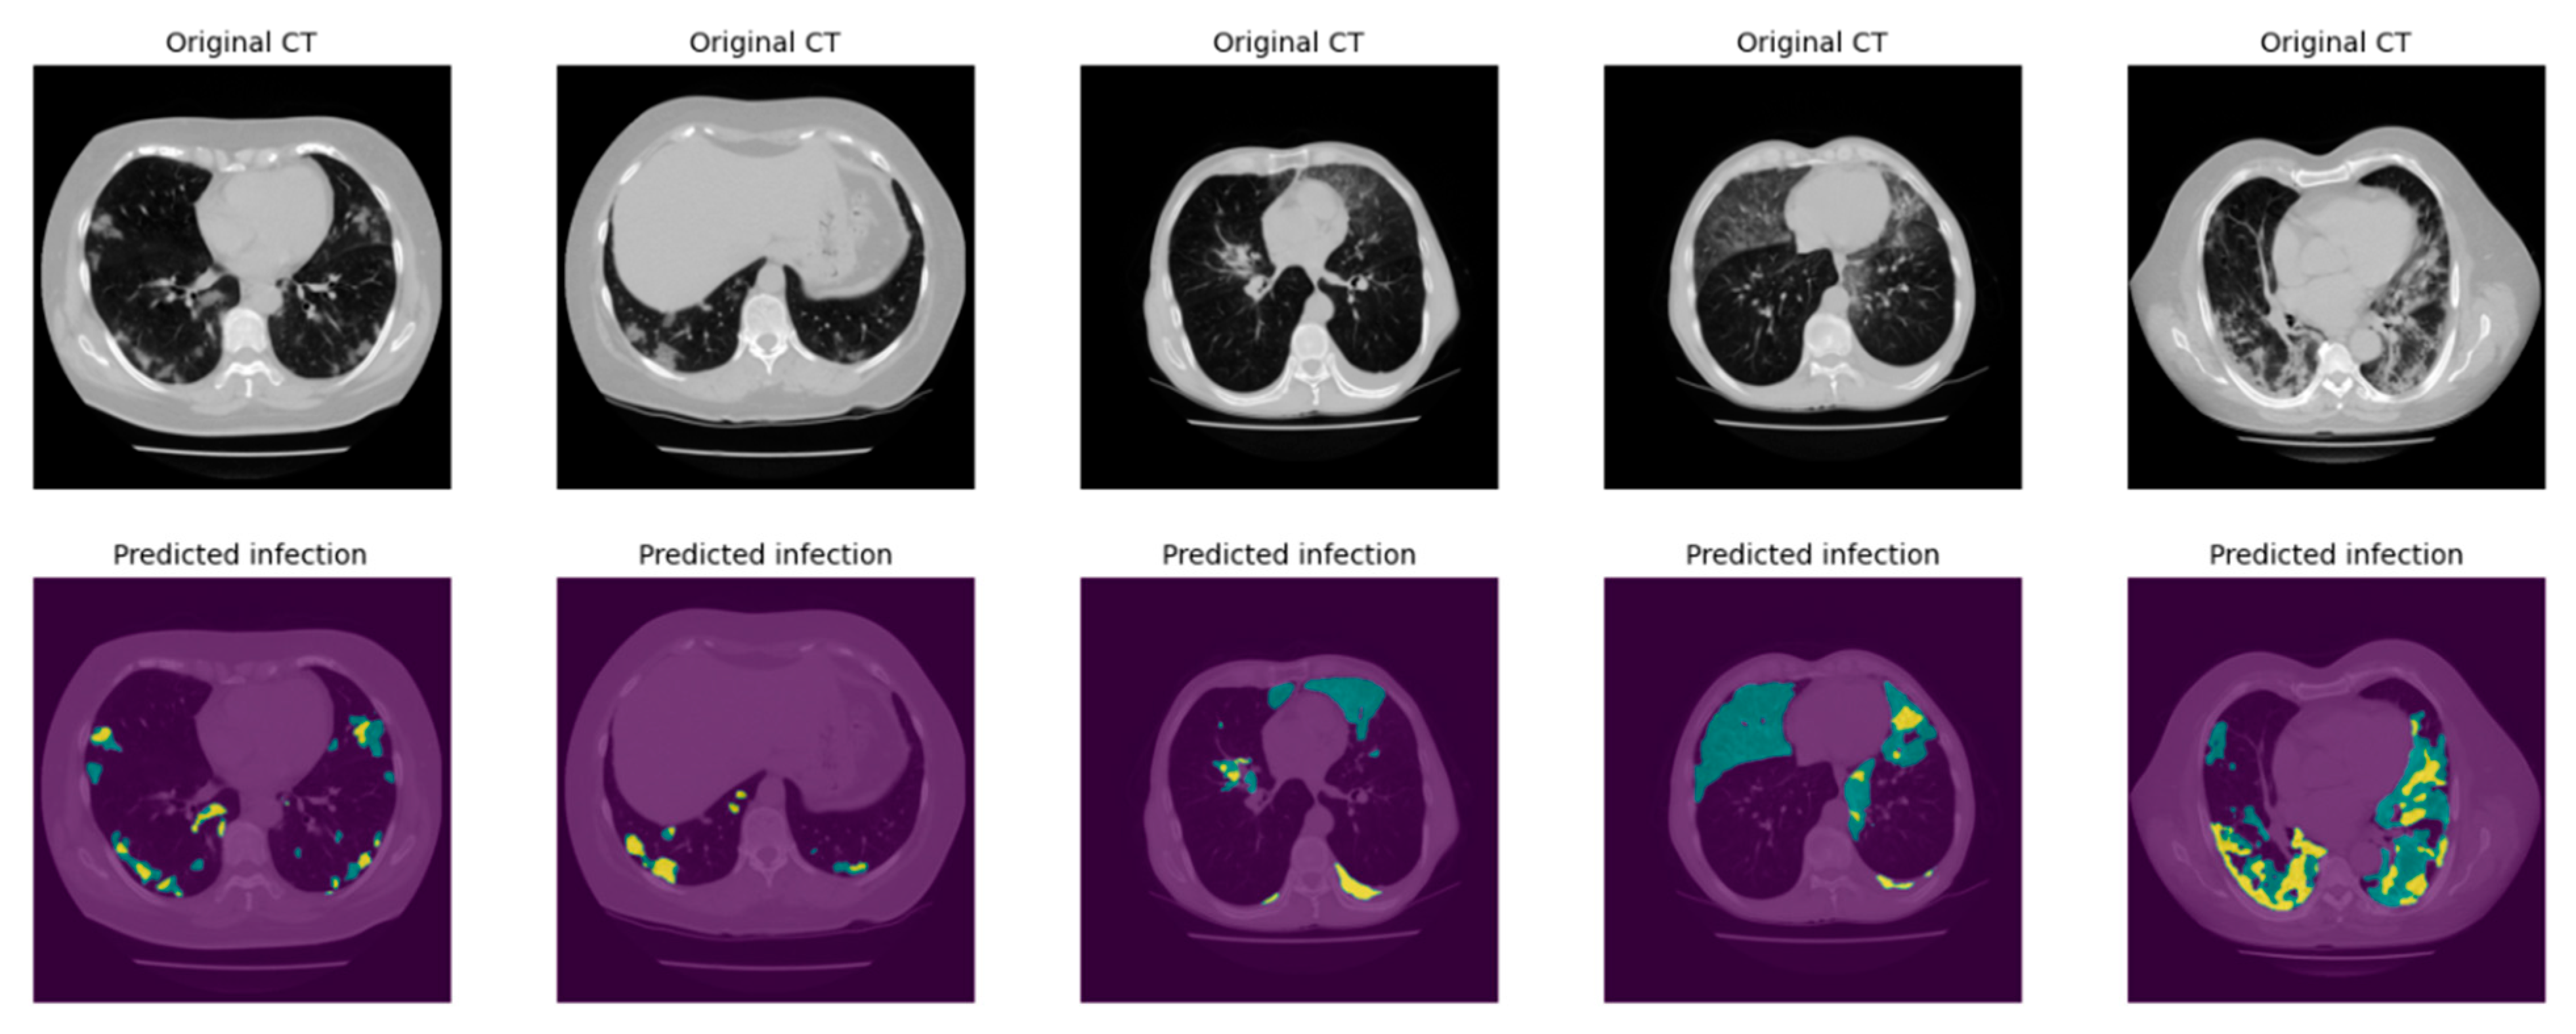

2.3.2. Infection Area Segmentation

2.3.3. Segmentation of GGO and Consolidation Patches

2.3.4. Integrated Model and GUI